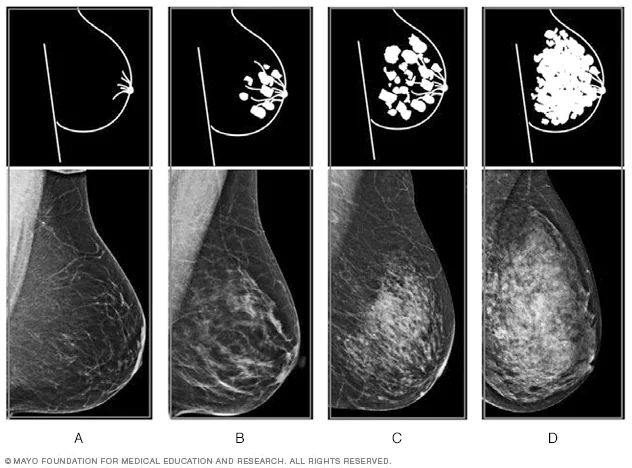

在美国,X线是乳腺癌筛查最主要的影像学方法。乳腺X线检查中,脂肪组织容易透视,呈深色透明状;纤维腺体组织难以透视,呈白色区域。因此放射科医生可以使用以下4种分类,描述女性的乳腺密度:

A)脂肪型:乳房几乎全由脂肪构成;

B)散在纤维腺体型:大部分乳腺是非致密的,存在一些分散的致密区域;

C)不均匀致密型:大部分乳腺是致密的,存在一些分散的非致密区域;

D)极度致密型:乳房几乎全由纤维腺体组织构成。

其中C和D被认为是致密型乳腺。乳腺致密是正常且常见的生理现象,大约40%~50%的美国女性乳腺属于致密型。年轻、体脂较少、处于怀孕或哺乳阶段、接受激素治疗的女性,乳腺可能更为致密。

乳腺密度的4种水平丨mayoclinic.org